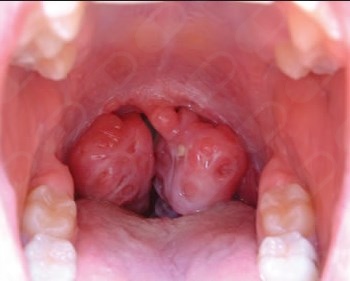

Mi enfoque profesional se basa en la atención personalizada, la empatía y el compromiso con el bienestar del paciente. Me especializo en cirugía endoscópica nasal, cirugía funcional y estética de la nariz, cirugía de cabeza y cuello, así como en el manejo quirúrgico de enfermedades de las amígdalas, incluyendo cirugía de amígdalas, indicada en casos de infecciones recurrentes, obstrucción respiratoria y otros padecimientos relacionados.